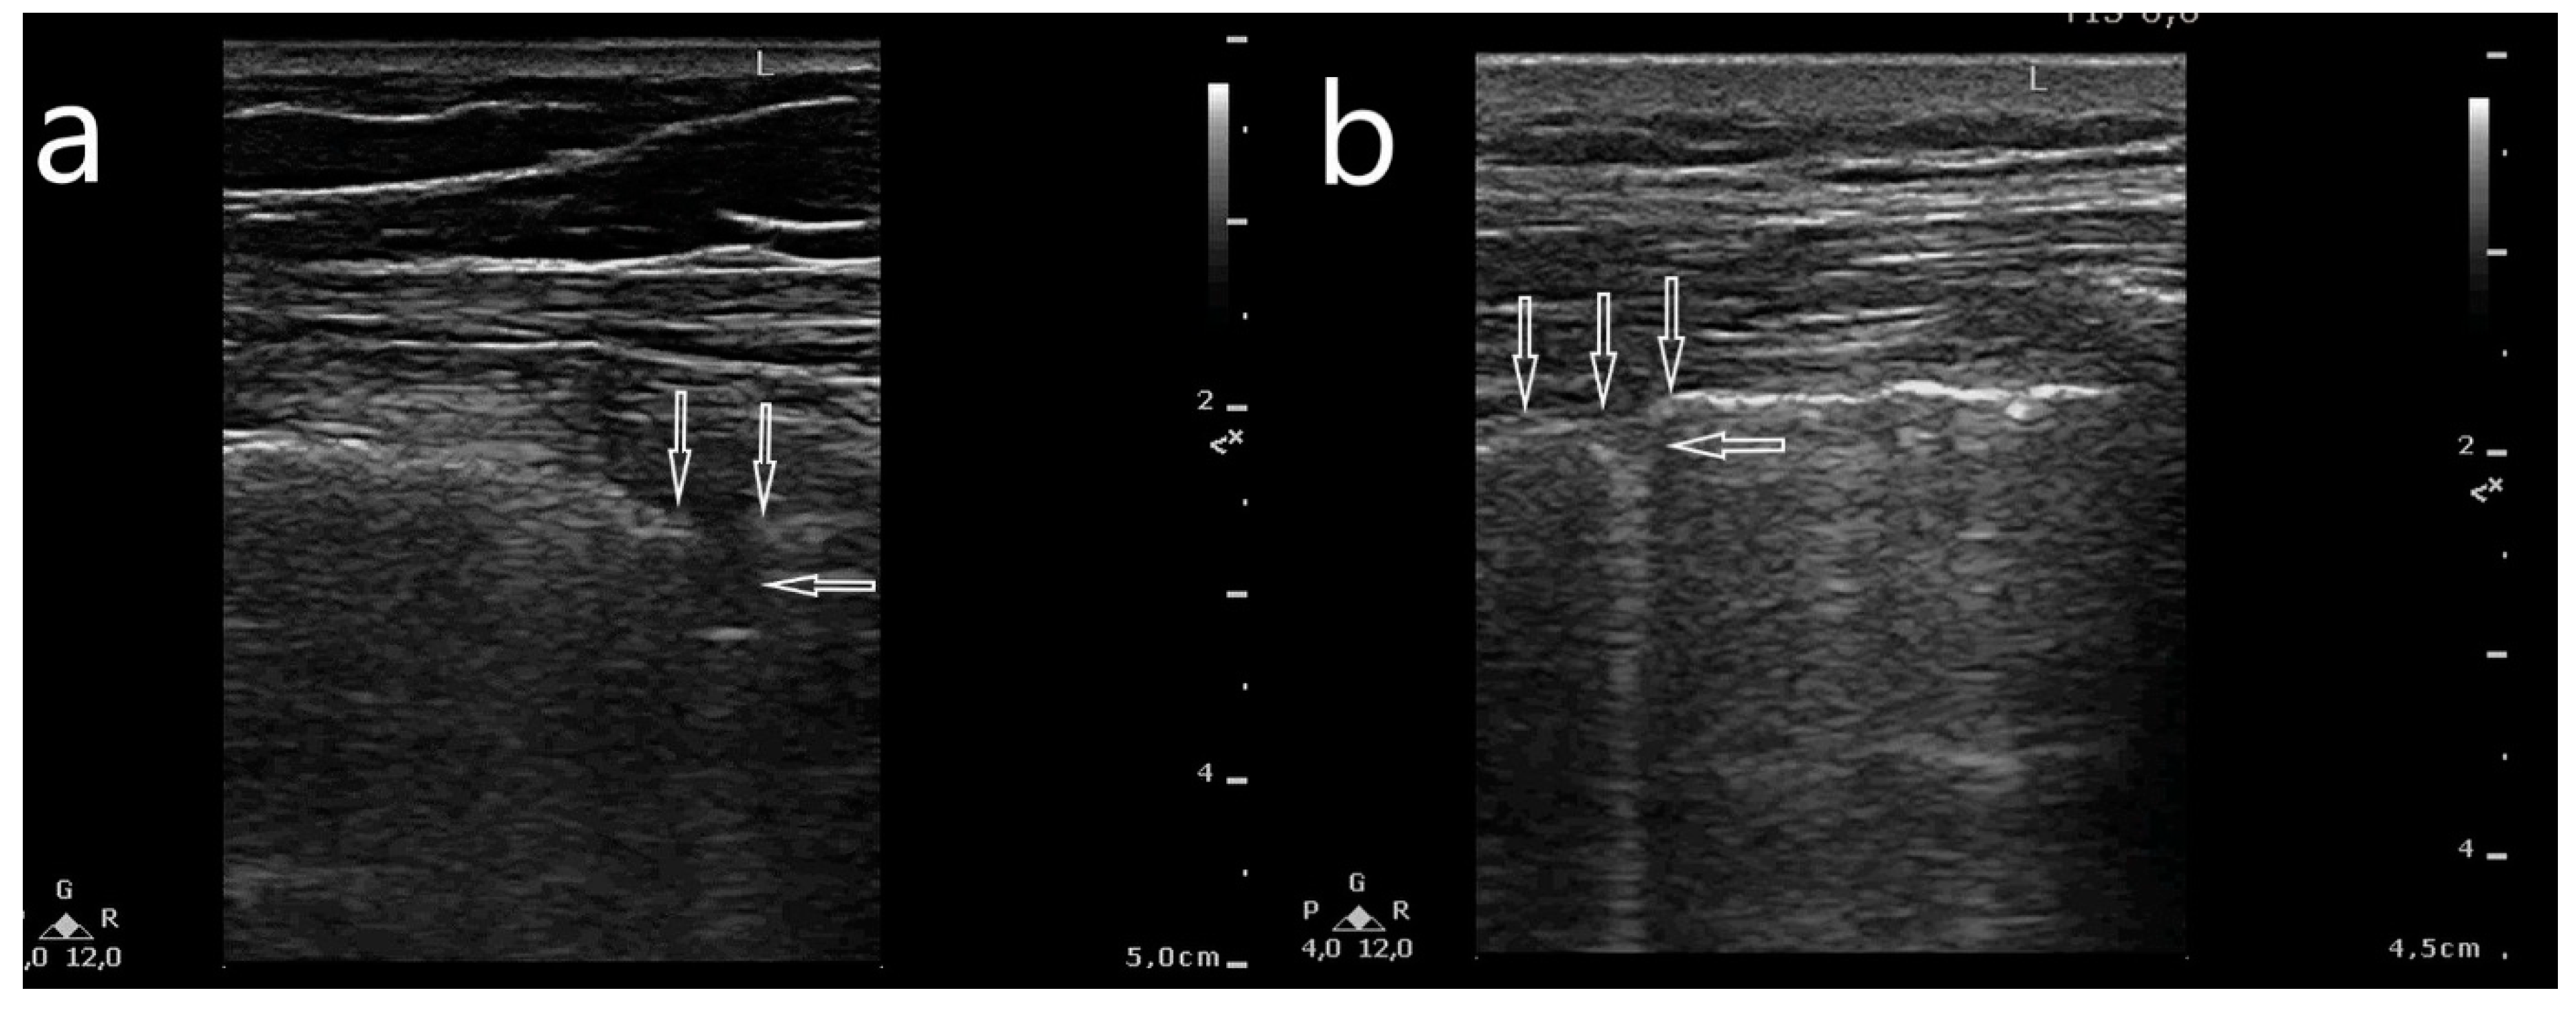

- Abnormalities within the pleural line (thickened, irregular, fragmented);

- Artifacts: multifocally located single B-line artifacts, multifocal multiple (confluent) B-line artifacts, bilateral and symmetrical B-lines, white lung, spared areas;

- Consolidations: small subpleural consolidations (up to 5 mm) accompanied with C-line artifacts, large consolidations involving segments and/or lobes, pleural effusion.